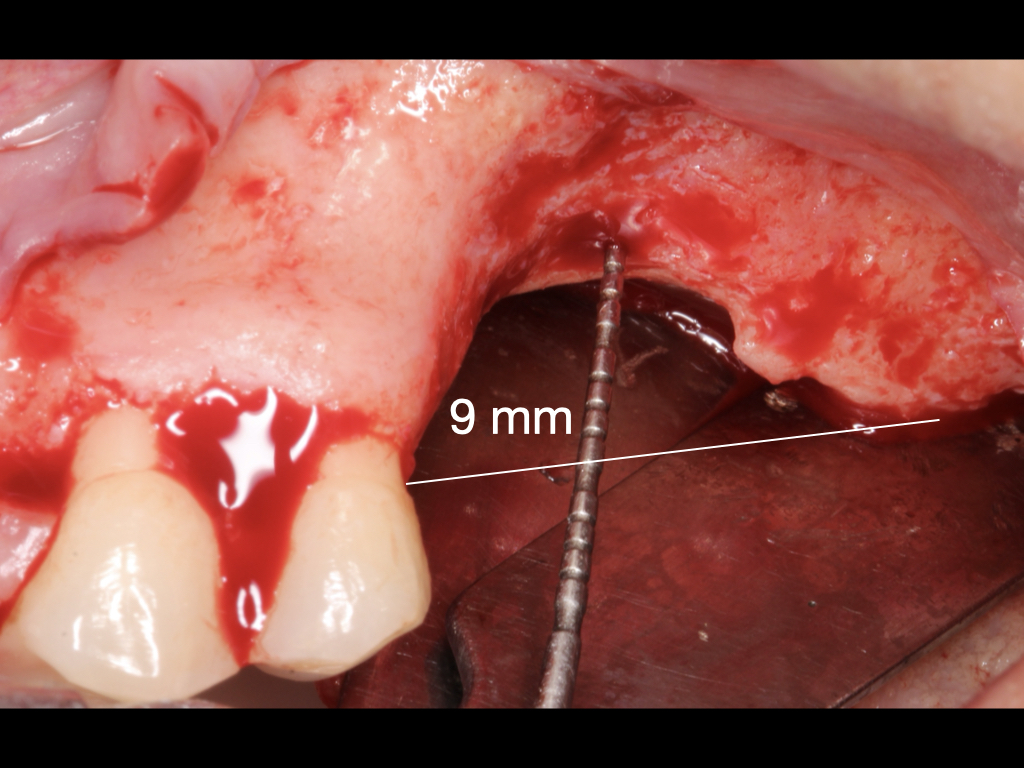

Figure 4.

After raising the flap a 9 mm vertical defect was found.